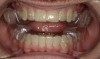

Intraoral scans were taken to document the patient's entire palate and bite registration. Scans were sent to the clinical team for the fabrication of a clear aligner/sleep appliance for the patient to wear; the chosen appliance fits over clear aligners, regardless of the tray number the patient may need (Figure 7 through Figure 11).

After the appliance was delivered, additional photographs were taken with the camera to ensure that the appliance was delivered as intended, to document the case, and to show the patient the ideal fit of the appliance in his mouth as instructions were reviewed with him.

Fig 8. The appliance worn during treatment, anterior view (Fig 8), right side view (Fig 9), left side view (Fig 10), and upper arch view (Fig 11).

Figure 8

Fig 9. The appliance worn during treatment, anterior view (Fig 8), right side view (Fig 9), left side view (Fig 10), and upper arch view (Fig 11).

Figure 9

Fig 10. The appliance worn during treatment, anterior view (Fig 8), right side view (Fig 9), left side view (Fig 10), and upper arch view (Fig 11).

Figure 10

Fig 11. The appliance worn during treatment, anterior view (Fig 8), right side view (Fig 9), left side view (Fig 10), and upper arch view (Fig 11).

Figure 11